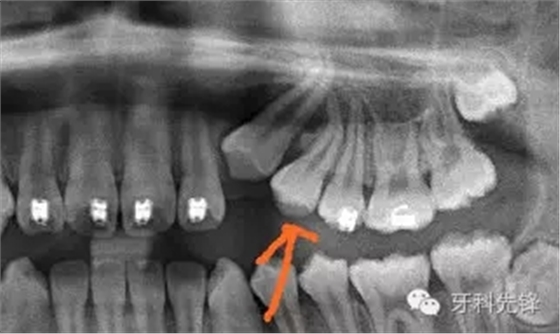

從X片上可以發(fā)現(xiàn)根尖1/3約有120°彎曲。